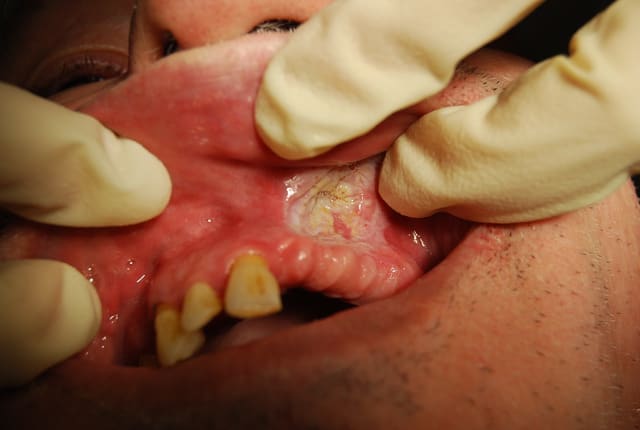

patient de 61 ans se presentant a la consultation pour rehabilitation prothetique

je vous laisse regarder les photos

la palpation nest pas douloureuse et on a une sensation d enfoncement.

le patient chique du tabac a l'endroit precis de la lesion

Diagnostic: kératose réactionnelle d'origine tabagique

CAT: palpation ganglionnaire, biopsie (surtout si doute de transformation maligne), dans tous les cas surveillance tous les 3 mois.

Pour rappel les signes de pré-cancérisation : lésion verruqueuse, inhomogène, contours irréguliers, mal limité, induration sous jacente.

Je pense qu'une biopsie de sécurité est envisageable vue la geule du truc !